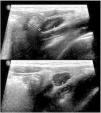

The World Health Organization defines the multisystem inflammatory syndrome in children (MIS-C) as a new syndrome reported in patients aged <19 years old who have a history of exposure to SARS-CoV-2. The onset of this syndrome is characterized by persistent fever that is associated with lethargy, abdominal pain, vomiting and/or diarrhea, and, less frequently, rash and conjunctivitis. The course and severity of the signs and symptoms vary; in some children, MIS-C worsens rapidly and can lead to hypotension, cariogenic shock, or even damage to multiple organs. The characteristic laboratory findings are elevated markers of inflammation and heart dysfunction. The most common radiological findings are cardiomegaly, pleural effusion, signs of heart failure, ascites, and inflammatory changes in the right iliac fossa. In the context of the current COVID-19 pandemic, radiologists need to know the clinical, laboratory, and radiological characteristics of this syndrome to ensure the correct diagnosis.

El síndrome inflamatorio multisistémico pediátrico vinculado a la COVID-19 (SIM-PedS) es, según la Organización Mundial de la Salud, un nuevo síndrome descrito en pacientes menores de 19 años con historia previa de exposición a SARS-CoV-2. La presentación inicial de este síndrome se caracteriza por fiebre persistente que asocia debilidad, dolor abdominal, vómitos y/o diarrea. Menos frecuentemente los pacientes pueden presentar también erupción cutánea y conjuntivitis. El cuadro clínico tiene expresividad y evolución variables, por lo que algunos pacientes pediátricos afectados pueden empeorar rápidamente, desarrollando desde hipotensión y shock cardiogénico a daño multiorgánico. Los hallazgos analíticos característicos del síndrome consisten en elevación de marcadores inflamatorios y disfunción cardíaca. Los hallazgos radiológicos más frecuentes son cardiomegalia, derrame pleural, signos de insuficiencia cardíaca, ascitis y cambios inflamatorios en la fosa ilíaca derecha. En la pandemia actual por COVID-19 es necesario que el radiólogo conozca las características clínico-analíticas y radiológicas de este síndrome para realizar un correcto diagnóstico.